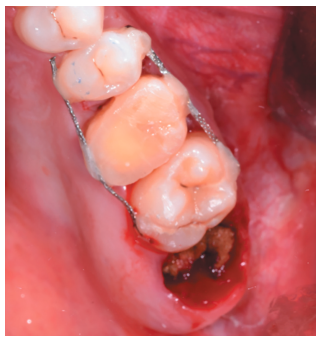

Caso clínico: se presenta el caso de un varón de 28 años, que acudió a consulta por la presencia de unos restos radiculares en localización de primer molar superior izquierdo. Se realizó un autotrasplante dental, siendo el diente donante el tercer molar superior izquierdo, que se trasplantó al alveolo del primer molar, mostrando buena evolución clínica y radiográfi ca.

Clinical case: a clinical case of a 28-yearold man is presented, who went to dental clinic for removal of left fi rst molar roots. An autotransplant was performed using left third molar as donor tooth, which was transplanted into fi rst molar alveolus, showing promising clinical and radiographic evolution.